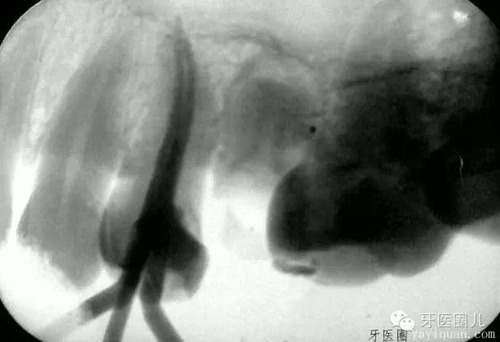

關(guān)于操作長度應(yīng)該短于X光片的終點(diǎn),也就是我們常說的“寧欠誤超”盡管意圖是好的,我們同行間經(jīng)??诳谙鄠?,但是短的限度是任意的,是錯(cuò)誤的信息和錯(cuò)誤的概念。牙根表面根尖孔的解剖位置和X光片上觀察到的根尖位置不相符,X光片不可能準(zhǔn)確的定位。相比X光根管測(cè)量儀就準(zhǔn)確的多,盡管有時(shí)不完美,但能準(zhǔn)確定位根尖孔的位置。

過短的根尖終點(diǎn)助長了碎屑的堆積和滯留也容易出現(xiàn)臺(tái)階和穿孔。操作長度短經(jīng)常導(dǎo)致根管治療的失敗;所以說根測(cè)儀在治療中是必須的,省不了的。